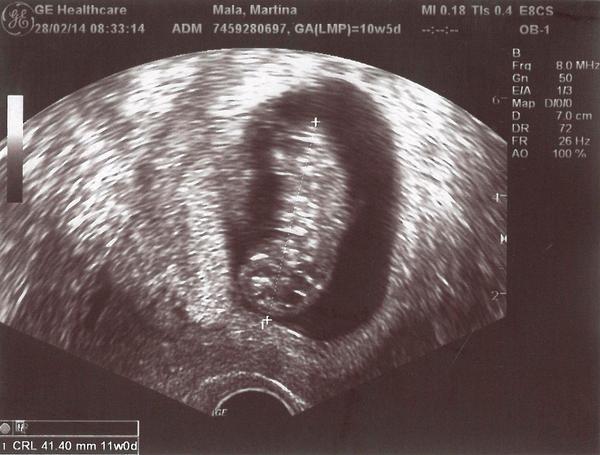

@jahodnice Ahoj,jo to znám..já na ní byla..a nic to nebylo,myslím tím bolest,ale to riziko tu je a já tě chápu,že nechceš nic riskovat... 😉 Tenkrát jsem měla před tím slabé krvácení a trochu jsem se bála,že by mohl být problém s mimi,takže jsem na to šla i schválně,abych věděla ,že to bude ok..A naštěstí bylo..hned jsem se uklidnila...

A když to jde se ujistit i jinak,tak proč ne,držím palce 🙂 😉